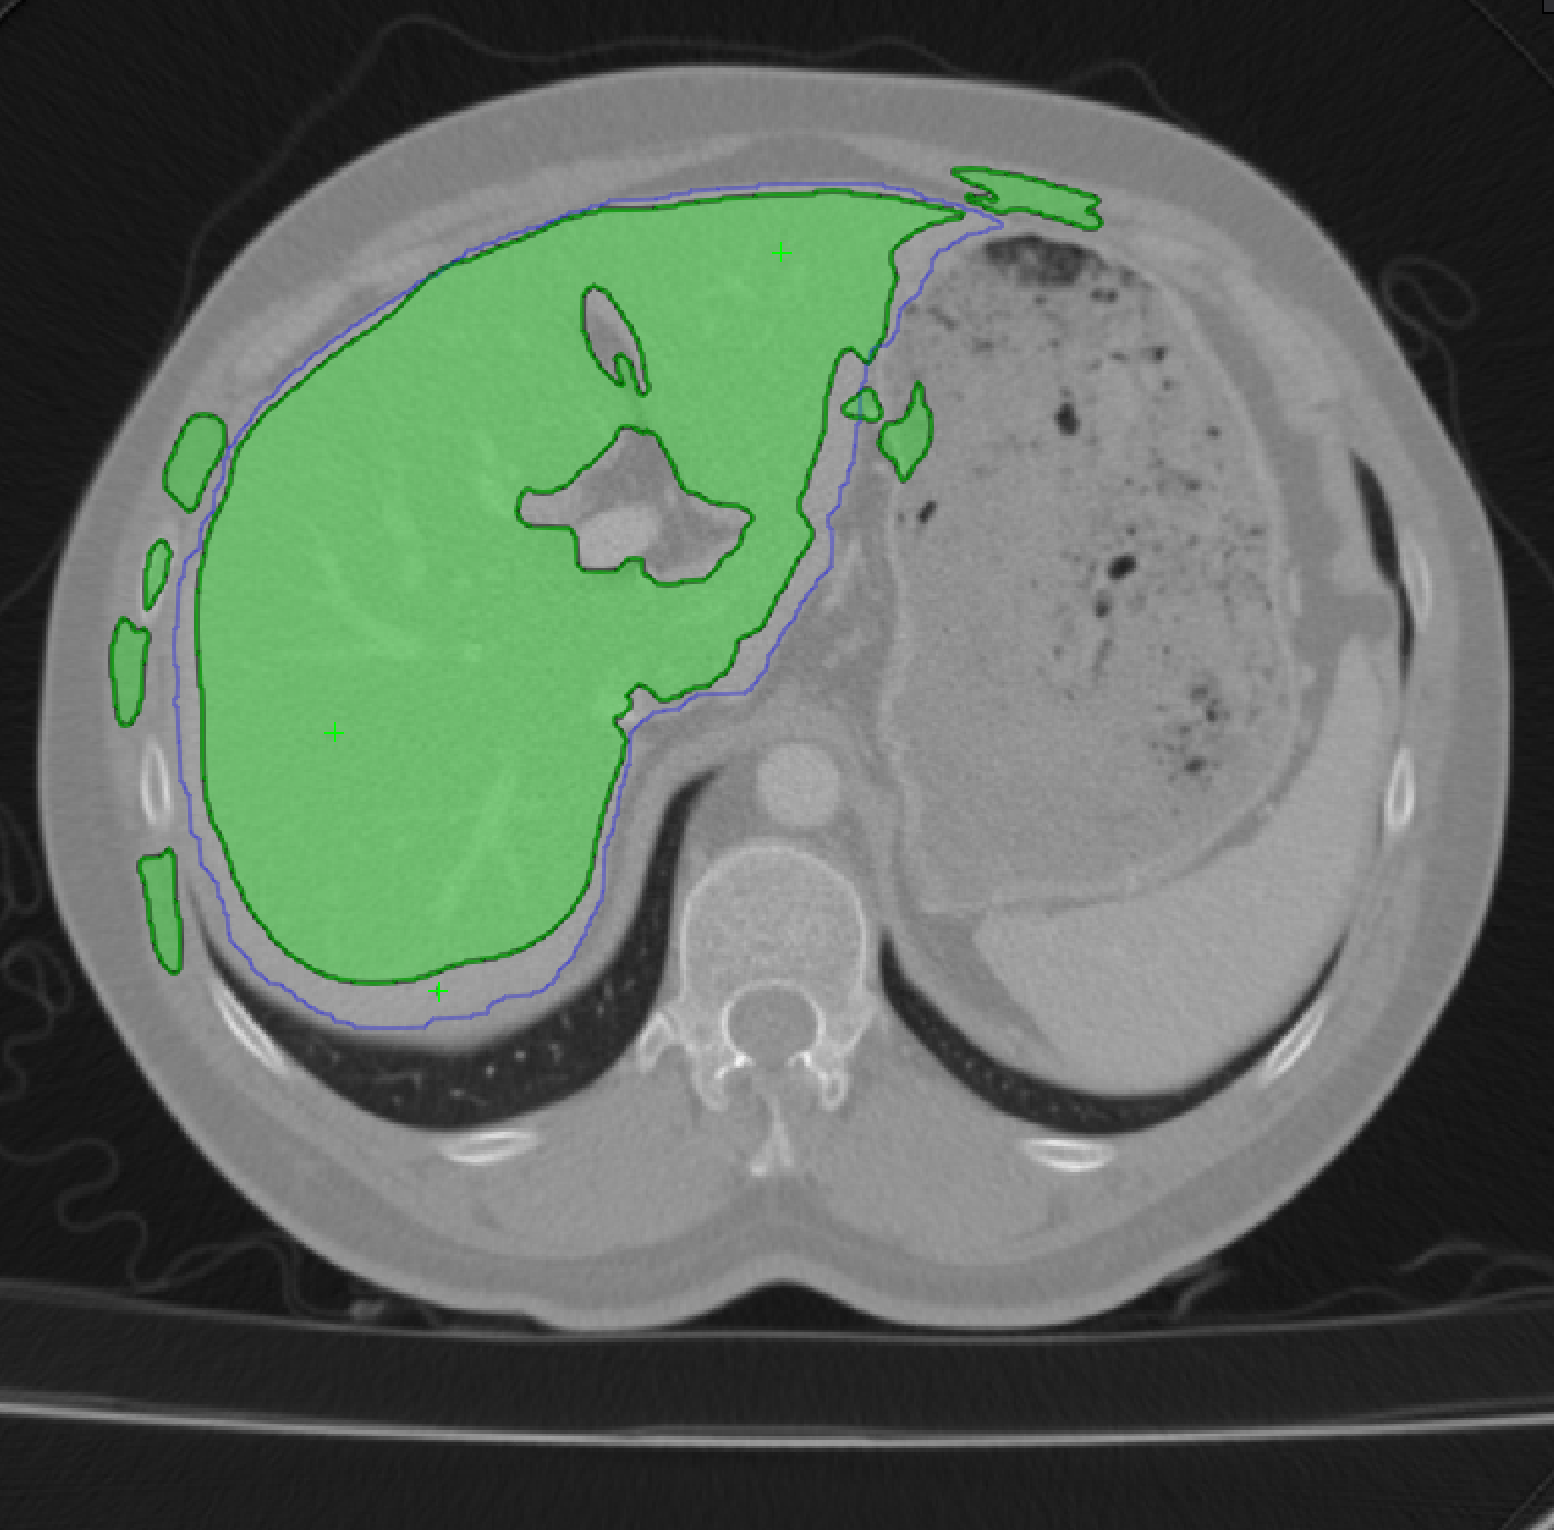

Minimizing during training ensures that the segmentations will be roughly correct. However, because the template can only be expected to provide a coarse depiction of the object, this is not enough. We therefore also minimize to force the network to yield accurate boundaries. Fig. 8 illustrates the influence of the and parameters on a real image. In practice, the results are insensitive to how they are chosen over a wide range. However, minimizing alone (=0) produces boundaries in that are exactly those of the template while minimizing alone (=1000) yields boundaries that exist in the image but are not necessarily those we are looking for. Minimizing a properly weighted sum of the two yields segmentations that conform to the template while matching actual image boundaries.

The template of Eq. 1 should approximately match the target structure. Hence, the annotator should supply points that are distributed across the object surface. These points are then used to deform the template. In practice, For structures of genus 0, we start from a simple spherical template but more complex ones are possible. As we increase the number of points, we get increasingly refined templates, as shown in Fig. 4.

To perform this deformation interactively, we developed a GUI that relies on Active Surface Models (ASMs) [26] implemented as a MITK [28] plugin. It lets the annotator supply a few points by clicking on 2D cross sections of the input image volume. The ASM then deforms the template in real-time and overlays it on the image data, both as 2D cross sections and 3D surface renderings. The annotator can then add more points wherever the deformed template is too far from the target organ’s boundary and iterate as often as necessary. This effectively puts the human in the loop in a painless and practical way. We illustrate this in a video that can be found in the supp. material.